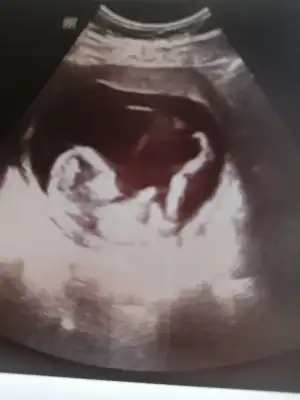

👫 11 yada 12 yada 13 hafta Nub usg nizi konumuza paylaşın

Arkadaşlar tahmin var mı? Özellikle ikra meyra :) Rabbim hayırlısını nasip etsin inşallah. 11+5